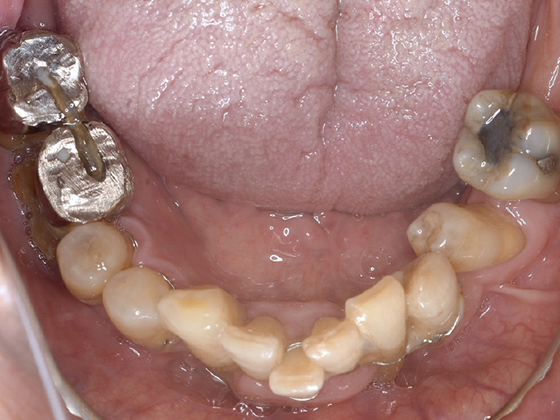

治療前

この症例では下顎の歯周病が特に進行していて、歯がクラグラで噛みにくい為、下の歯を抜歯してオールオン4で治療、上は特に歯周病が進行している左側の大臼歯を抜歯して経過観察することにしました。